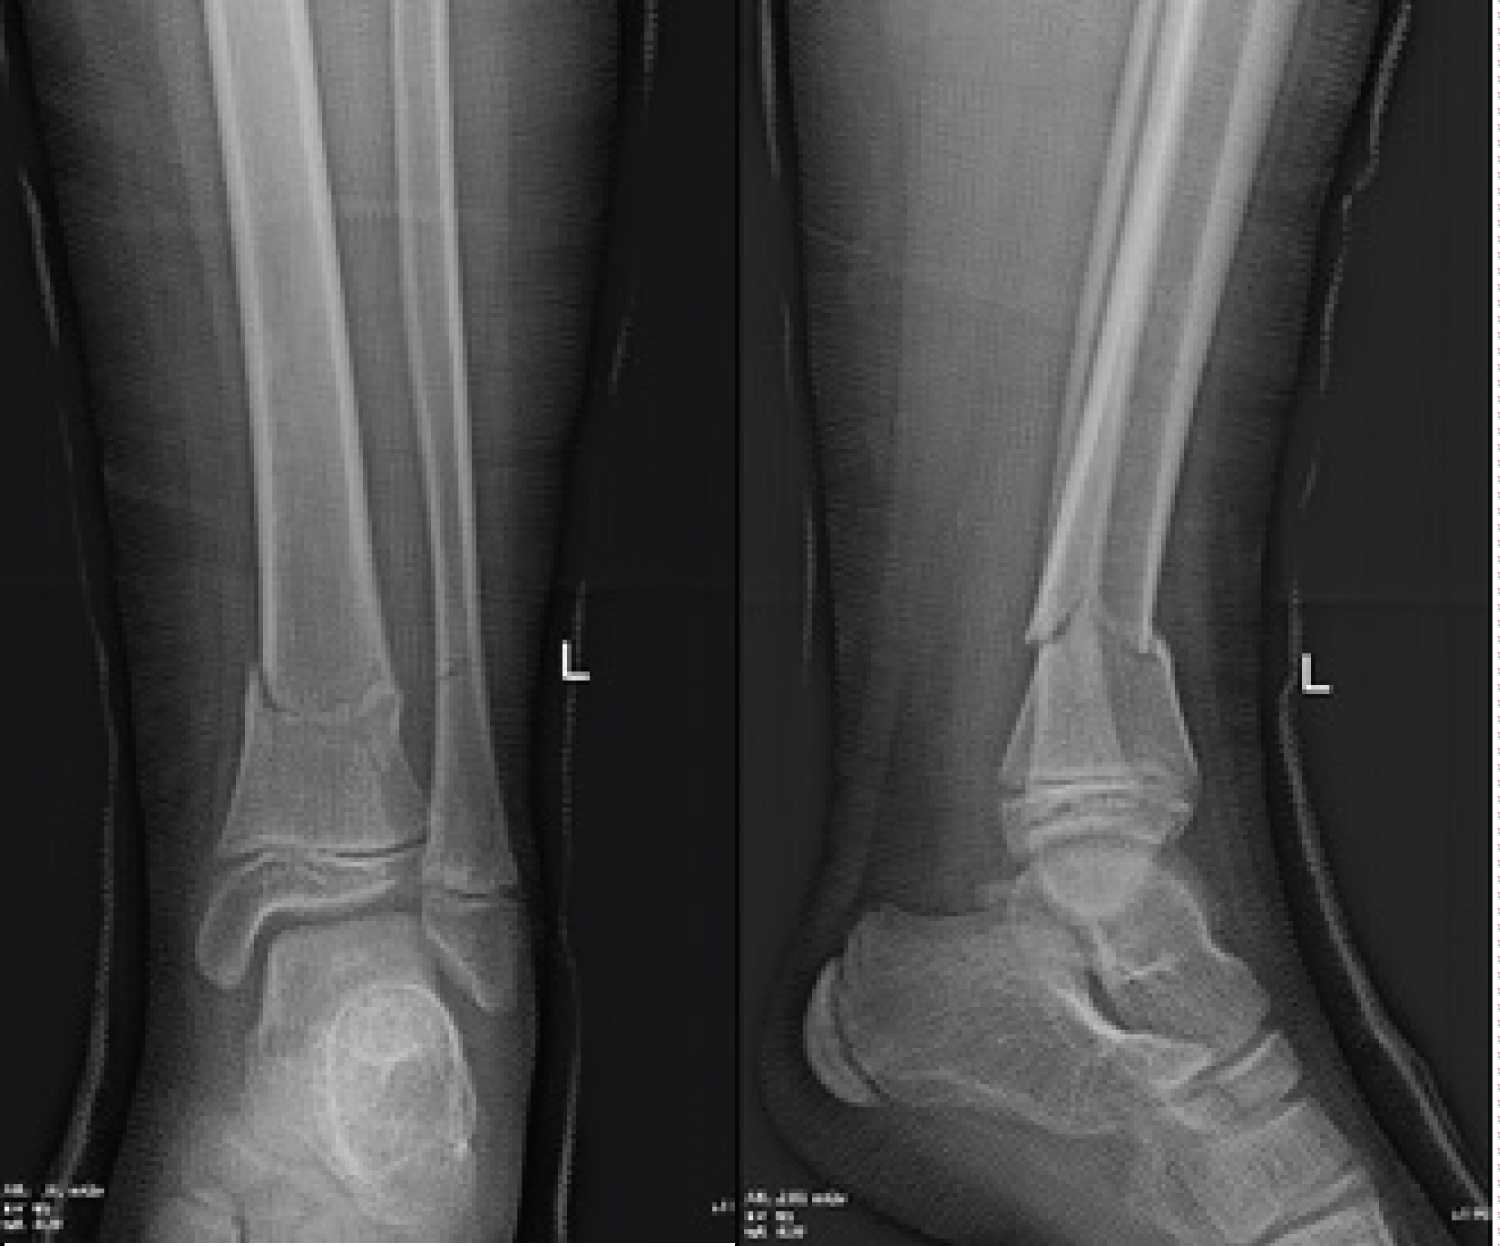

AP and lateral radiographs revealed a fracture of the distal tibial metaphysis with no significant displacement neither in the frontal nor in the sagittal plane. There was a limited recurvatum of 5 degrees with no varus/valgus deformity comparing to the other limb. There was also a concomitant fibular fracture (Figure 1). No osseous lesions were detected in the joints cranially or caudally to the fracture.

Figure 1: Comparative AP and lateral radiographs at presentation showing the barely displaced fractures of distal tibia and distal fibula metaphysis. View Figure 1